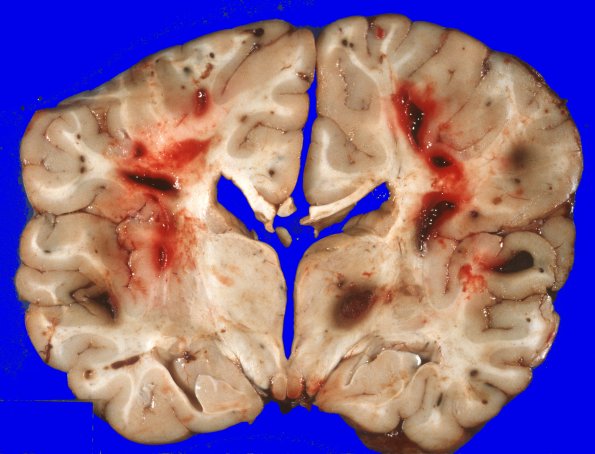

There is bilaterally symmetrical cerebral edema causing flattening of the gyri and narrowing of the sulci over both hemispheres. Cross sections of the bilateral cerebral hemispheres disclose multiple well circumscribed areas of hemorrhage, many at the cortical gray/white junction. These measure from approximately 1 mm to 2 cms in diameter. In some cases, the central portion of the hemorrhage appears to be made up of a pale appearing substance.